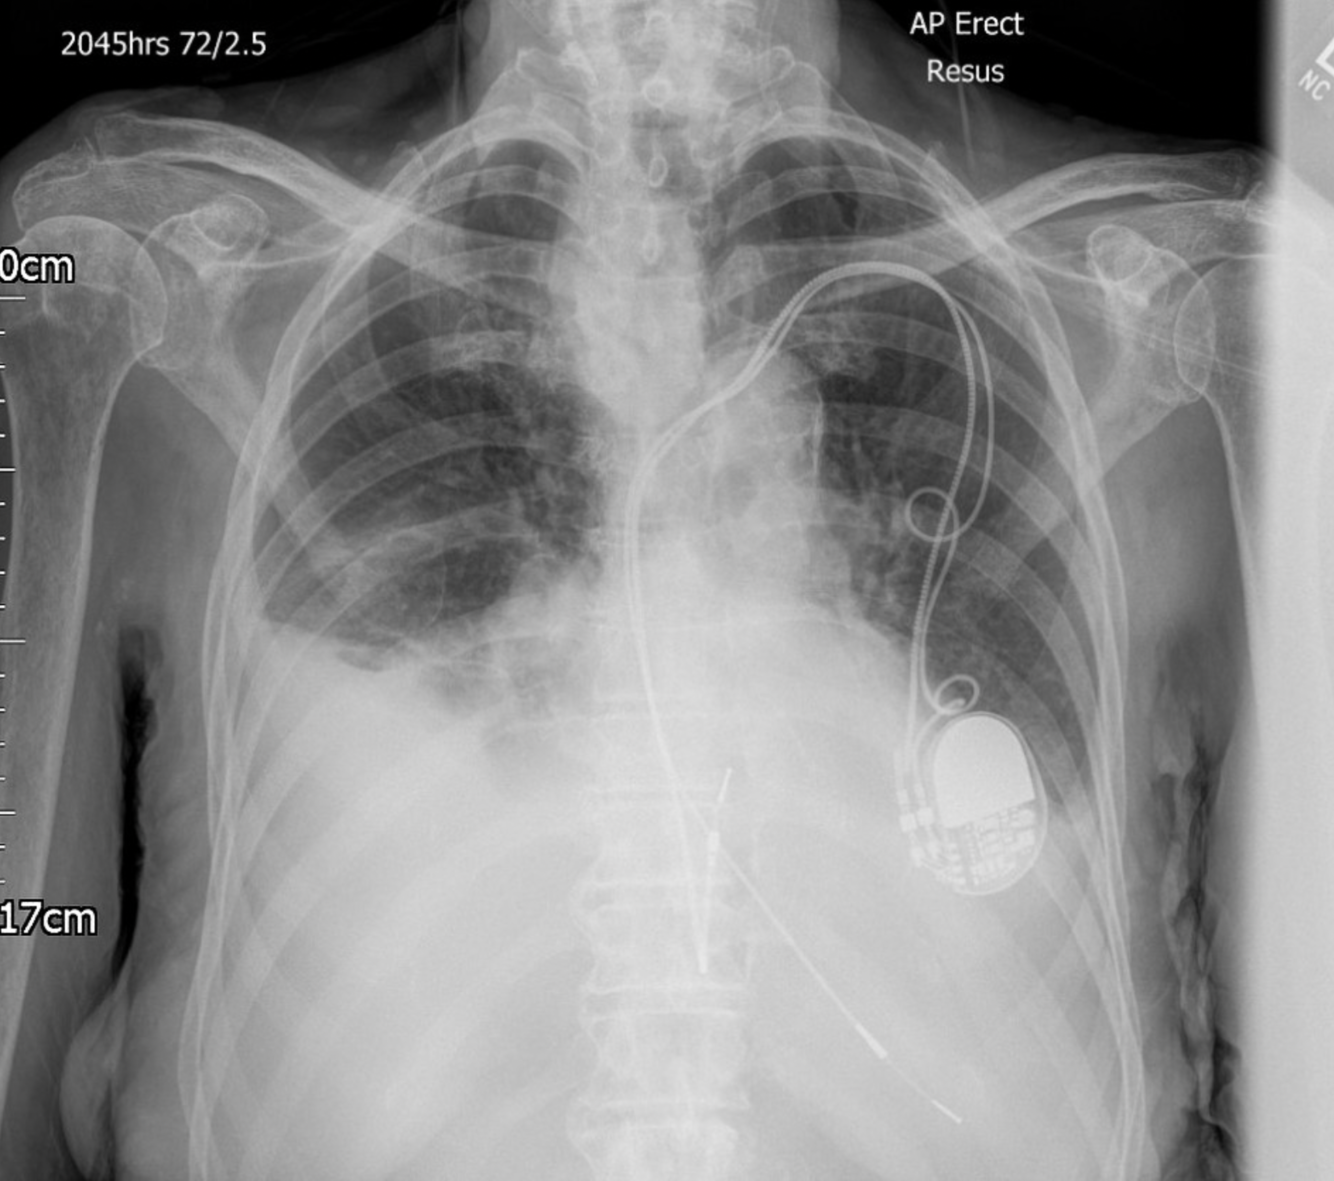

3

Q

A

Atrial lead fracture (right by box), right pleural effusion,